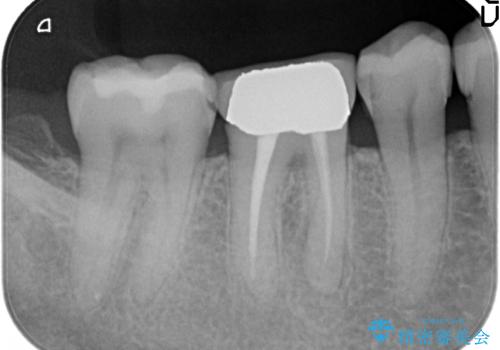

咬んだ時の違和感 顕微鏡で発見された歯の穴を処置し、かみ合わせを回復する

- 再根管治療にて発見されたパーフォレーションを修復し、改めてかぶせ物を製作する。

レントゲンに大きな問題がなくても、実際に顕微鏡で見ることにより様々な問題が露呈することはよくあります。

再治療の繰り返しにより歯に穴があいてしまっていることもよくありますが、このような深い位置の穴は、特殊なセメントで封鎖することにより非常に経過良く処置することができます。